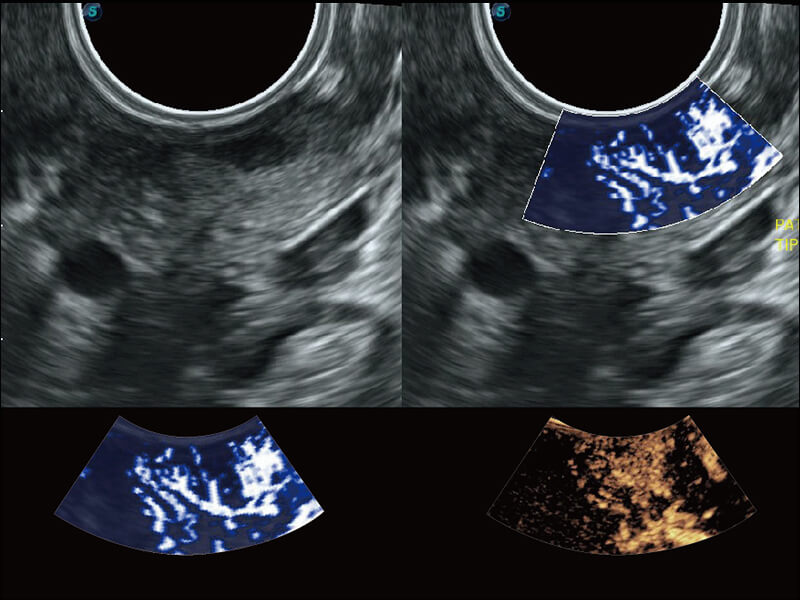

成像功能

S60探头工艺,从前端信号处理每一个环节采集无损声学数据,真实还原组织原貌,再现解剖细节。

超宽频带技术,为容积成像带来优质的二维图像基础,为您呈现丰富的结构细节,栩栩如生地展示宝宝的宫内形态以及各种组织的立体结构。